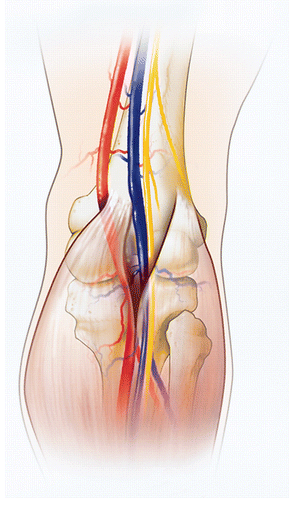

Anatomical abnormalities involving the medial head of gastrocnemius muscle result in popliteal artery entrapment syndrome.

popliteal artery entrapment syndrome